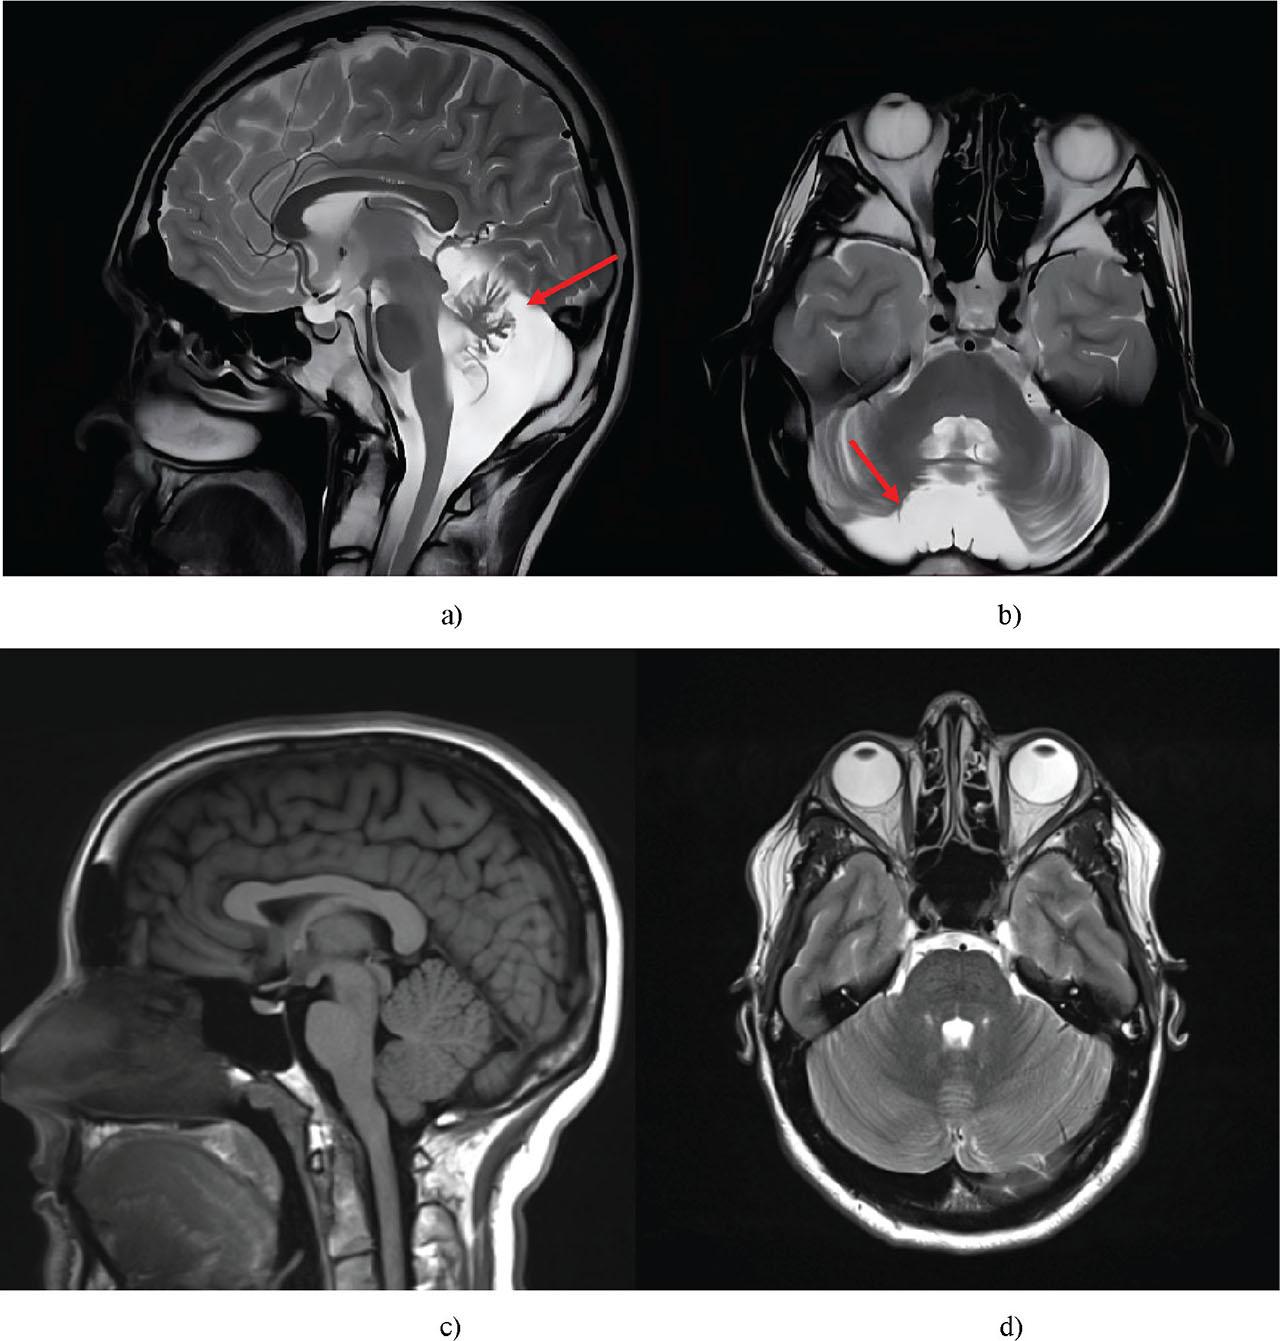

| Brain MRI | Identification of cerebellar atrophy, enlargement of the cisterna magna |